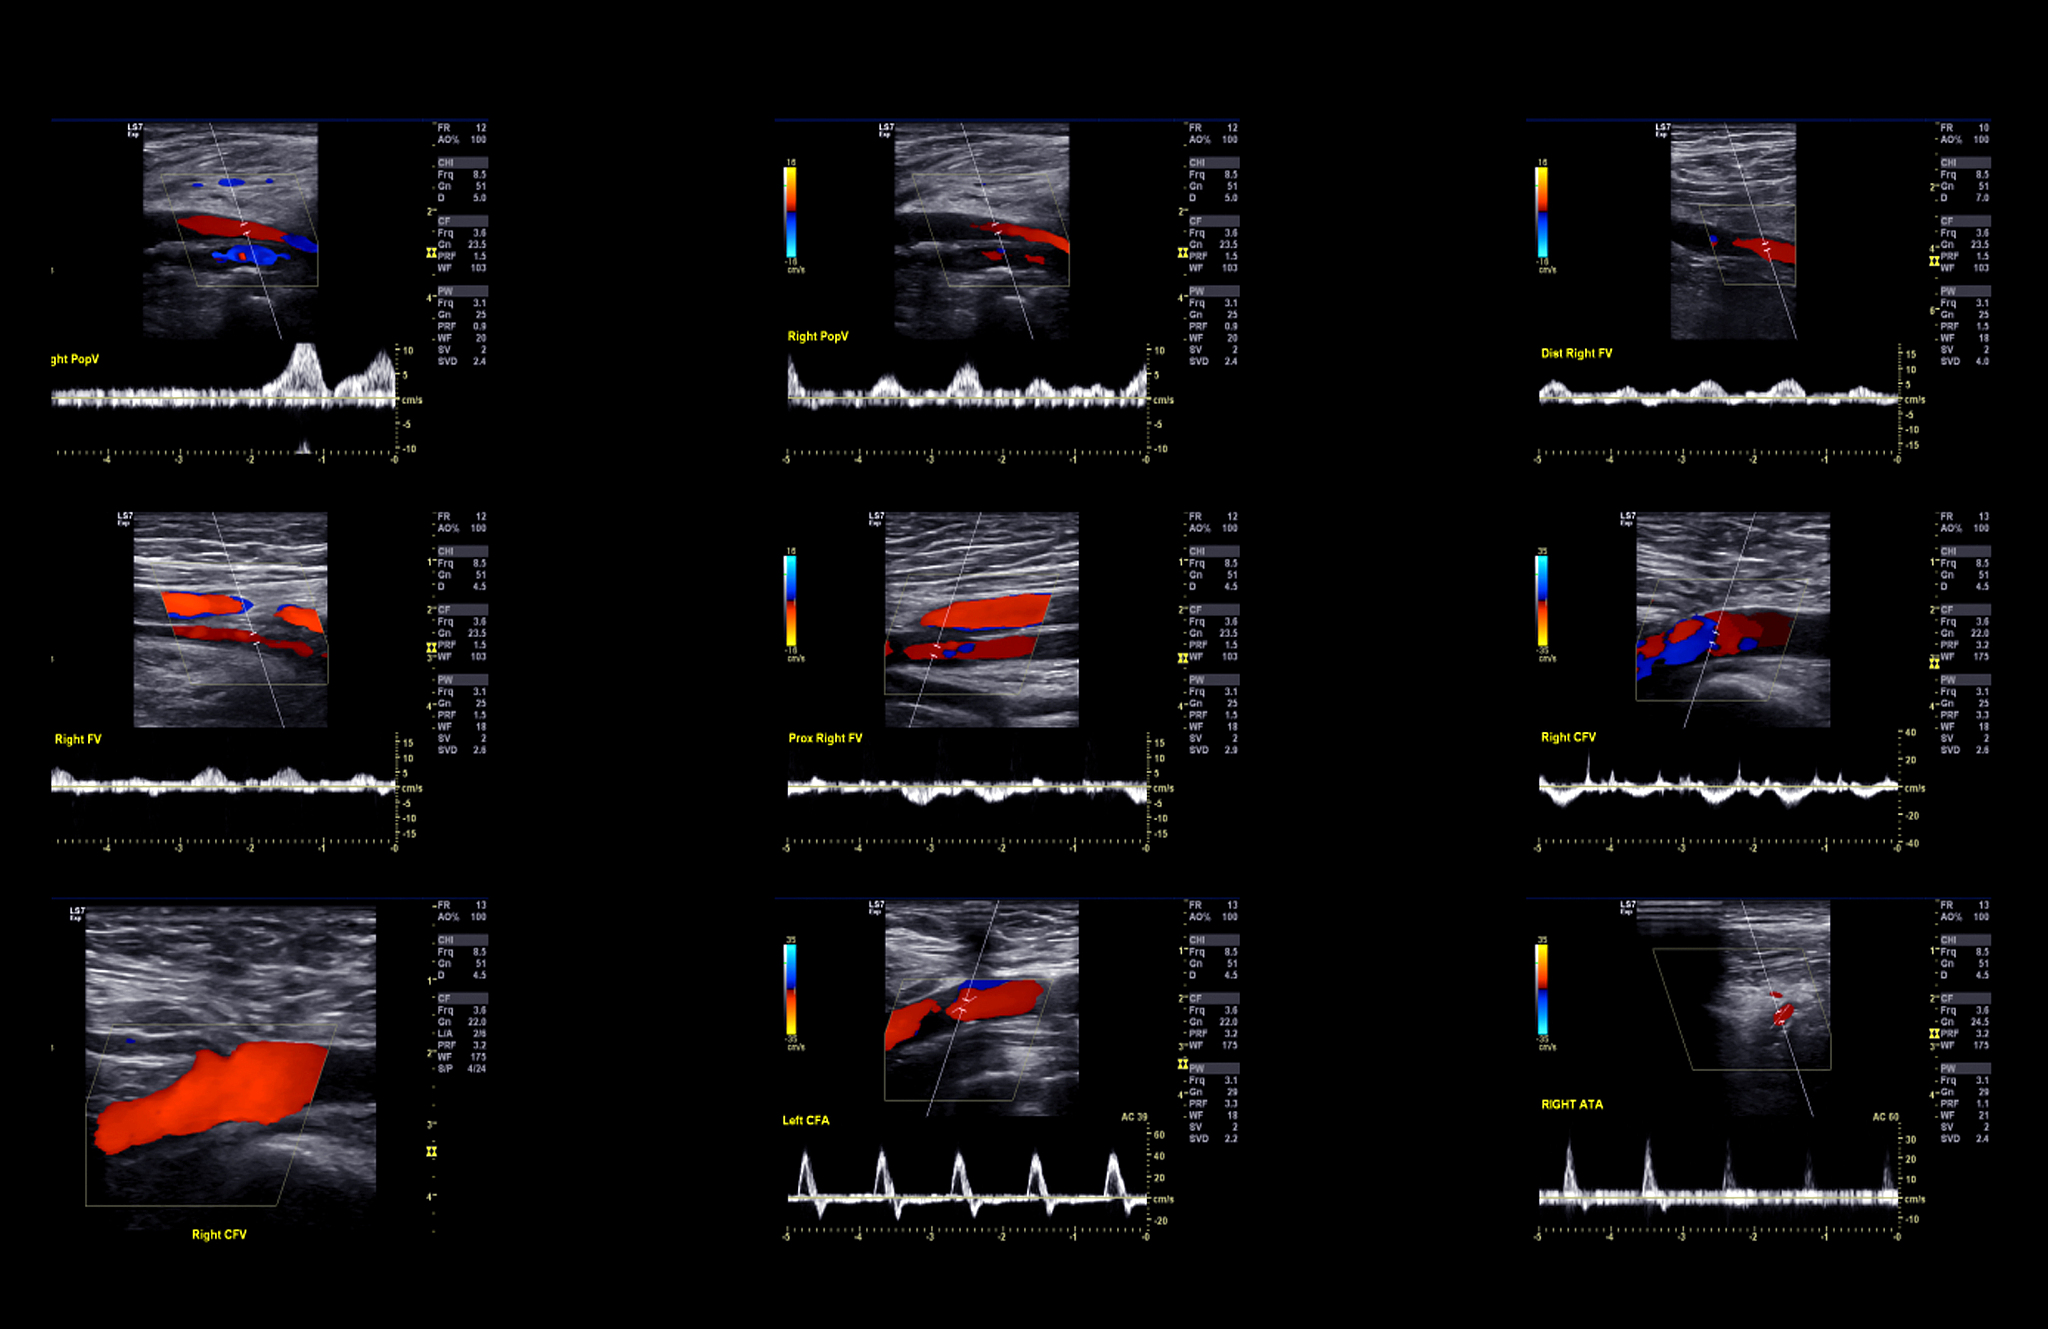

ChatGPT 可以应用于超声医学科的许多方面,包括但不限于以下几个方面:\n\n1. 超声图像解释和分析:ChatGPT 可以帮助医生解释和分析超声图像,提供对异常结构或病变的诊断建议。医生可以向 ChatGPT 提供超声图像,并获得关于图像特征、病变类型和可能的诊断的反馈。\n\n2. 病例讨论和知识共享:ChatGPT 可以作为一个交流平台,医生可以通过与 ChatGPT 进行对话来讨论和分享有关超声医学的病例和知识。医生可以提出问题、分享经验,并获得 ChatGPT 的回答和反馈。\n\n3. 疾病诊断和治疗建议:ChatGPT 可以帮助医生在超声医学诊断中提供辅助意见。医生可以向 ChatGPT 提供病人的症状、病史和超声图像,然后获得可能的诊断和治疗建议。\n\n4. 继续教育和培训:ChatGPT 可以用作超声医学科的继续教育和培训工具。医学生、实习生和住院医师可以与 ChatGPT 进行交互,提问关于超声医学的问题,并获得详细的解释和指导。\n\n5. 研究和数据分析:ChatGPT 可以帮助研究人员在超声医学领域进行数据分析和研究。研究人员可以向 ChatGPT 提供超声图像和相关数据,并获得有关数据分析、结果解释和研究设计的反馈。\n\n需要注意的是,虽然 ChatGPT 在超声医学科的许多方面具有潜力,但它仍然是一个自然语言处理模型,无法替代医生的专业知识和判断。在实际应用中,医生应始终将 ChatGPT 提供的建议和意见作为参考,并结合自己的临床经验和专业知识进行决策。